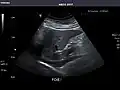

Renal ultrasonography

Ultrasonography of the kidneys is essential in the diagnosis and management of kidney-related diseases. The kidneys are easily examined, and most pathological changes in the kidneys are distinguishable with ultrasound.[7]

Kidneys: Right and left kidneys measure 11.5 cm and 12 cm in length respectively. No hydronephrosis. Small left lower pole kidney cyst.

Left kidney -